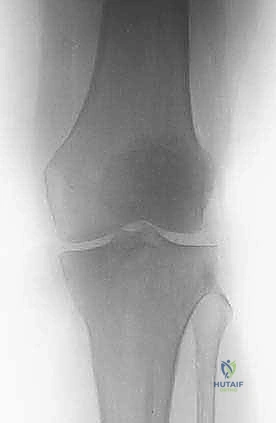

3. الجزء السفلي من عظم الفخذ (Distal Femur)

هذا الجزء يتسع ليشكل اللقمتين الفخذيتين (Condyles) اللتين تتمفصلان مع عظم الظنبوب (القصبة) لتكوين مفصل الركبة. النقائل في هذه المنطقة تؤثر بشكل مباشر على ميكانيكا الركبة وتسبب آلاماً شديدة عند ثني أو فرد الساق. الجراحة هنا تتطلب دقة متناهية للحفاظ على أربطة الركبة (الصليبية والجانبية) أو استبدال المفصل بالكامل بمفصل صناعي للأورام إذا كان التدمير العظمي واسعاً.

- الأشعة السينية العادية (X-rays): هي الخطوة الأولى دائماً. تظهر النقائل الحالة للعظم كبقع داكنة (ثقوب) في العظم، بينما تظهر النقائل البانية كبقع بيضاء كثيفة. الأشعة السينية ضرورية لتقييم خطر الكسر.